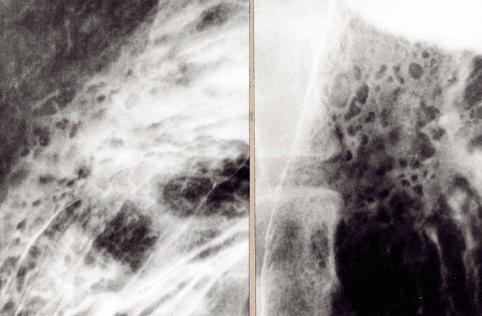

疾病(病理主体)的分类恶性上皮性肿瘤/腺癌

部位(按器官分)胃(部位)/体部

检查方法X线

肿瘤的肉眼分类0型(表在型)/IIc型(IIc)

肿瘤最大直径40以上

肿瘤的深度m